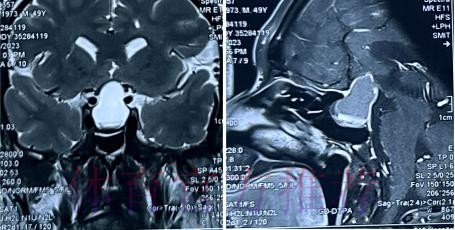

在高速对抗的现代足球里 现场肉眼和赛后情绪往往会放大对伤情的判断 一名球员倒地呻吟或无法坚持比赛 很容易被解读为韧带断裂 或肌肉严重撕裂 但真正决定恢复周期的关键因素 通常要到核磁共振检查之后才会明朗 因为核磁能在较早阶段清晰显示软组织 肌肉 韧带以及骨结构的微小损伤情况 对伤情做出更接近真相的分级判断 塞巴略斯此次就是典型案例 初步观感可能让人联想到更严重的伤病 但核磁提示伤情相对可控 没有出现完全断裂或大面积撕裂 也就意味着他不需要漫长的康复旅程 只要遵循医学建议 科学负荷管理 就有机会用较短的时间重新回到训练场和比赛中

足球历史上 不乏因为伤情评估偏差而延误治疗的例子 某些球员在初诊时被认定为普通拉伤 结果因为没有进行完整的核磁共振检查 继续带伤出战 最终发展成严重撕裂 被迫长时间缺阵 从竞技层面来看 一次错误判断 可能直接改写一个赛季的走向 也可能在球员的职业生涯里留下不可逆转的隐患 与这些案例对照 塞巴略斯这次的过程显得更为规范 受伤后迅速接受医学影像检查 医疗团队根据结果评估伤情等级 给出清晰恢复计划 俱乐部层面则通过官方渠道适度释出消息 在 保护隐私与满足公众关切之间 取得平衡 对比之下 可以看出 现代职业俱乐部在伤病管理上的专业程度 已远超十几年前更多依赖经验和肉眼判断的时代 同时也提醒公众 不要被比赛画面中的瞬间表现完全左右 而是学会等待更权威的医学信息

经核磁共振检查确认 塞巴略斯伤情没有预期严重 这一结果从某种意义上是一种系统胜利 首先是医疗系统的胜利 医疗团队在第一时间介入 选择最合适的影像学手段 明确伤情边界 避免了盲目乐观或过度保守 其次是管理系统的胜利 俱乐部没有急于利用球员的意愿 扮演所谓硬汉形象 而是尊重科学节奏 为他预留足够的恢复空间 再次是沟通系统的胜利 球员 经纪人 医疗小组和教练组之间保持信息畅通 能够在保护球员未来和保证球队眼前成绩之间找到平衡点 正是这些系统共同作用 才让一次看似危机四伏的受伤 逐步转化为可控 可恢复的阶段性波折